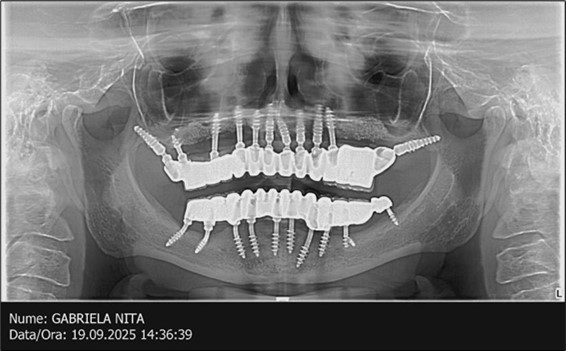

June 2022: Patient presented to our clinic for immediate-loading implant treatment At the time of presentation in 06. 2022, radiologically, advanced peri- implantitis is observed around the implants, with loss of native bone in the affected distal areas (Figure 1)

Figure 1.Panoramic overview picture before rehabilitation 06.2022

Figure 3.Panoramic pictures after removal of implants affected by peri-implantitis, extractions, alveolar crest regularization, and insertion of corticobasal and TPG implants (07.2022)